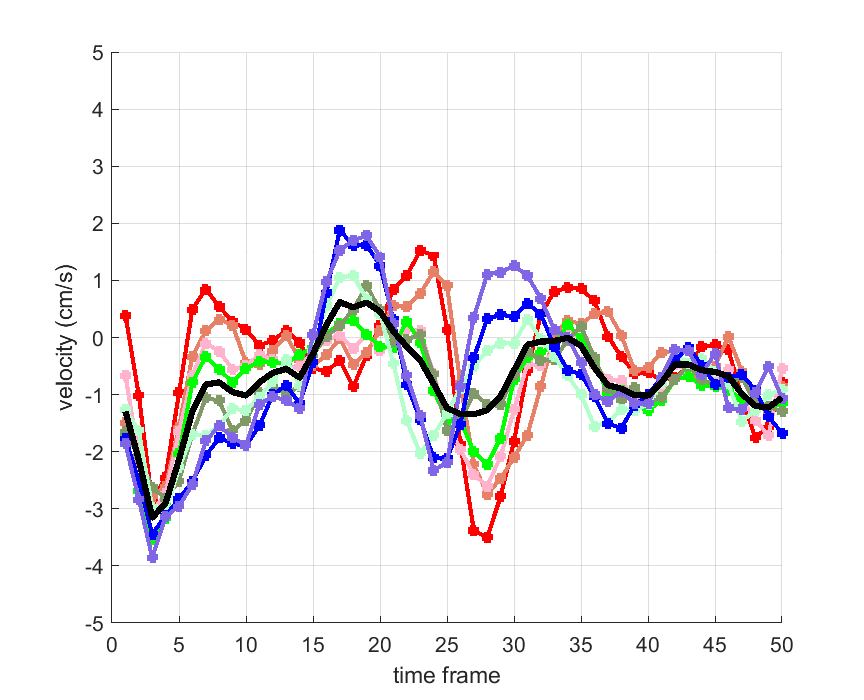

Time courses of the estimated translational component per subject, frame, slice and volume along the 3 velocity directions x, y and z are presented in Fig.6 - Fig.8.